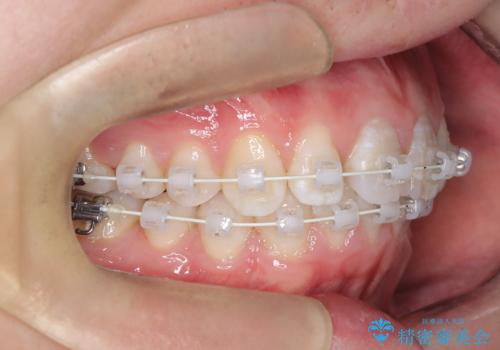

【ワイヤー矯正 11ヵ月で矯正終了!】歯のでこぼこを治したい!

- ワイヤー(審美装置)

- 11ヶ月

- 「歯のでこぼこを治したい 1年くらいで矯正を終わらせたい」を主訴に来院された患者様です。

叢生量は多く無く歯の傾斜も標準傾斜だったので歯は抜かずにワイヤー矯正で治療を行いました。

左側は2級傾向が強く臼歯の遠心移動をご提案しましたが、1年以内に矯正を終わらせたいという患者様のご意向で希望されず叢生を改善する矯正となりました。